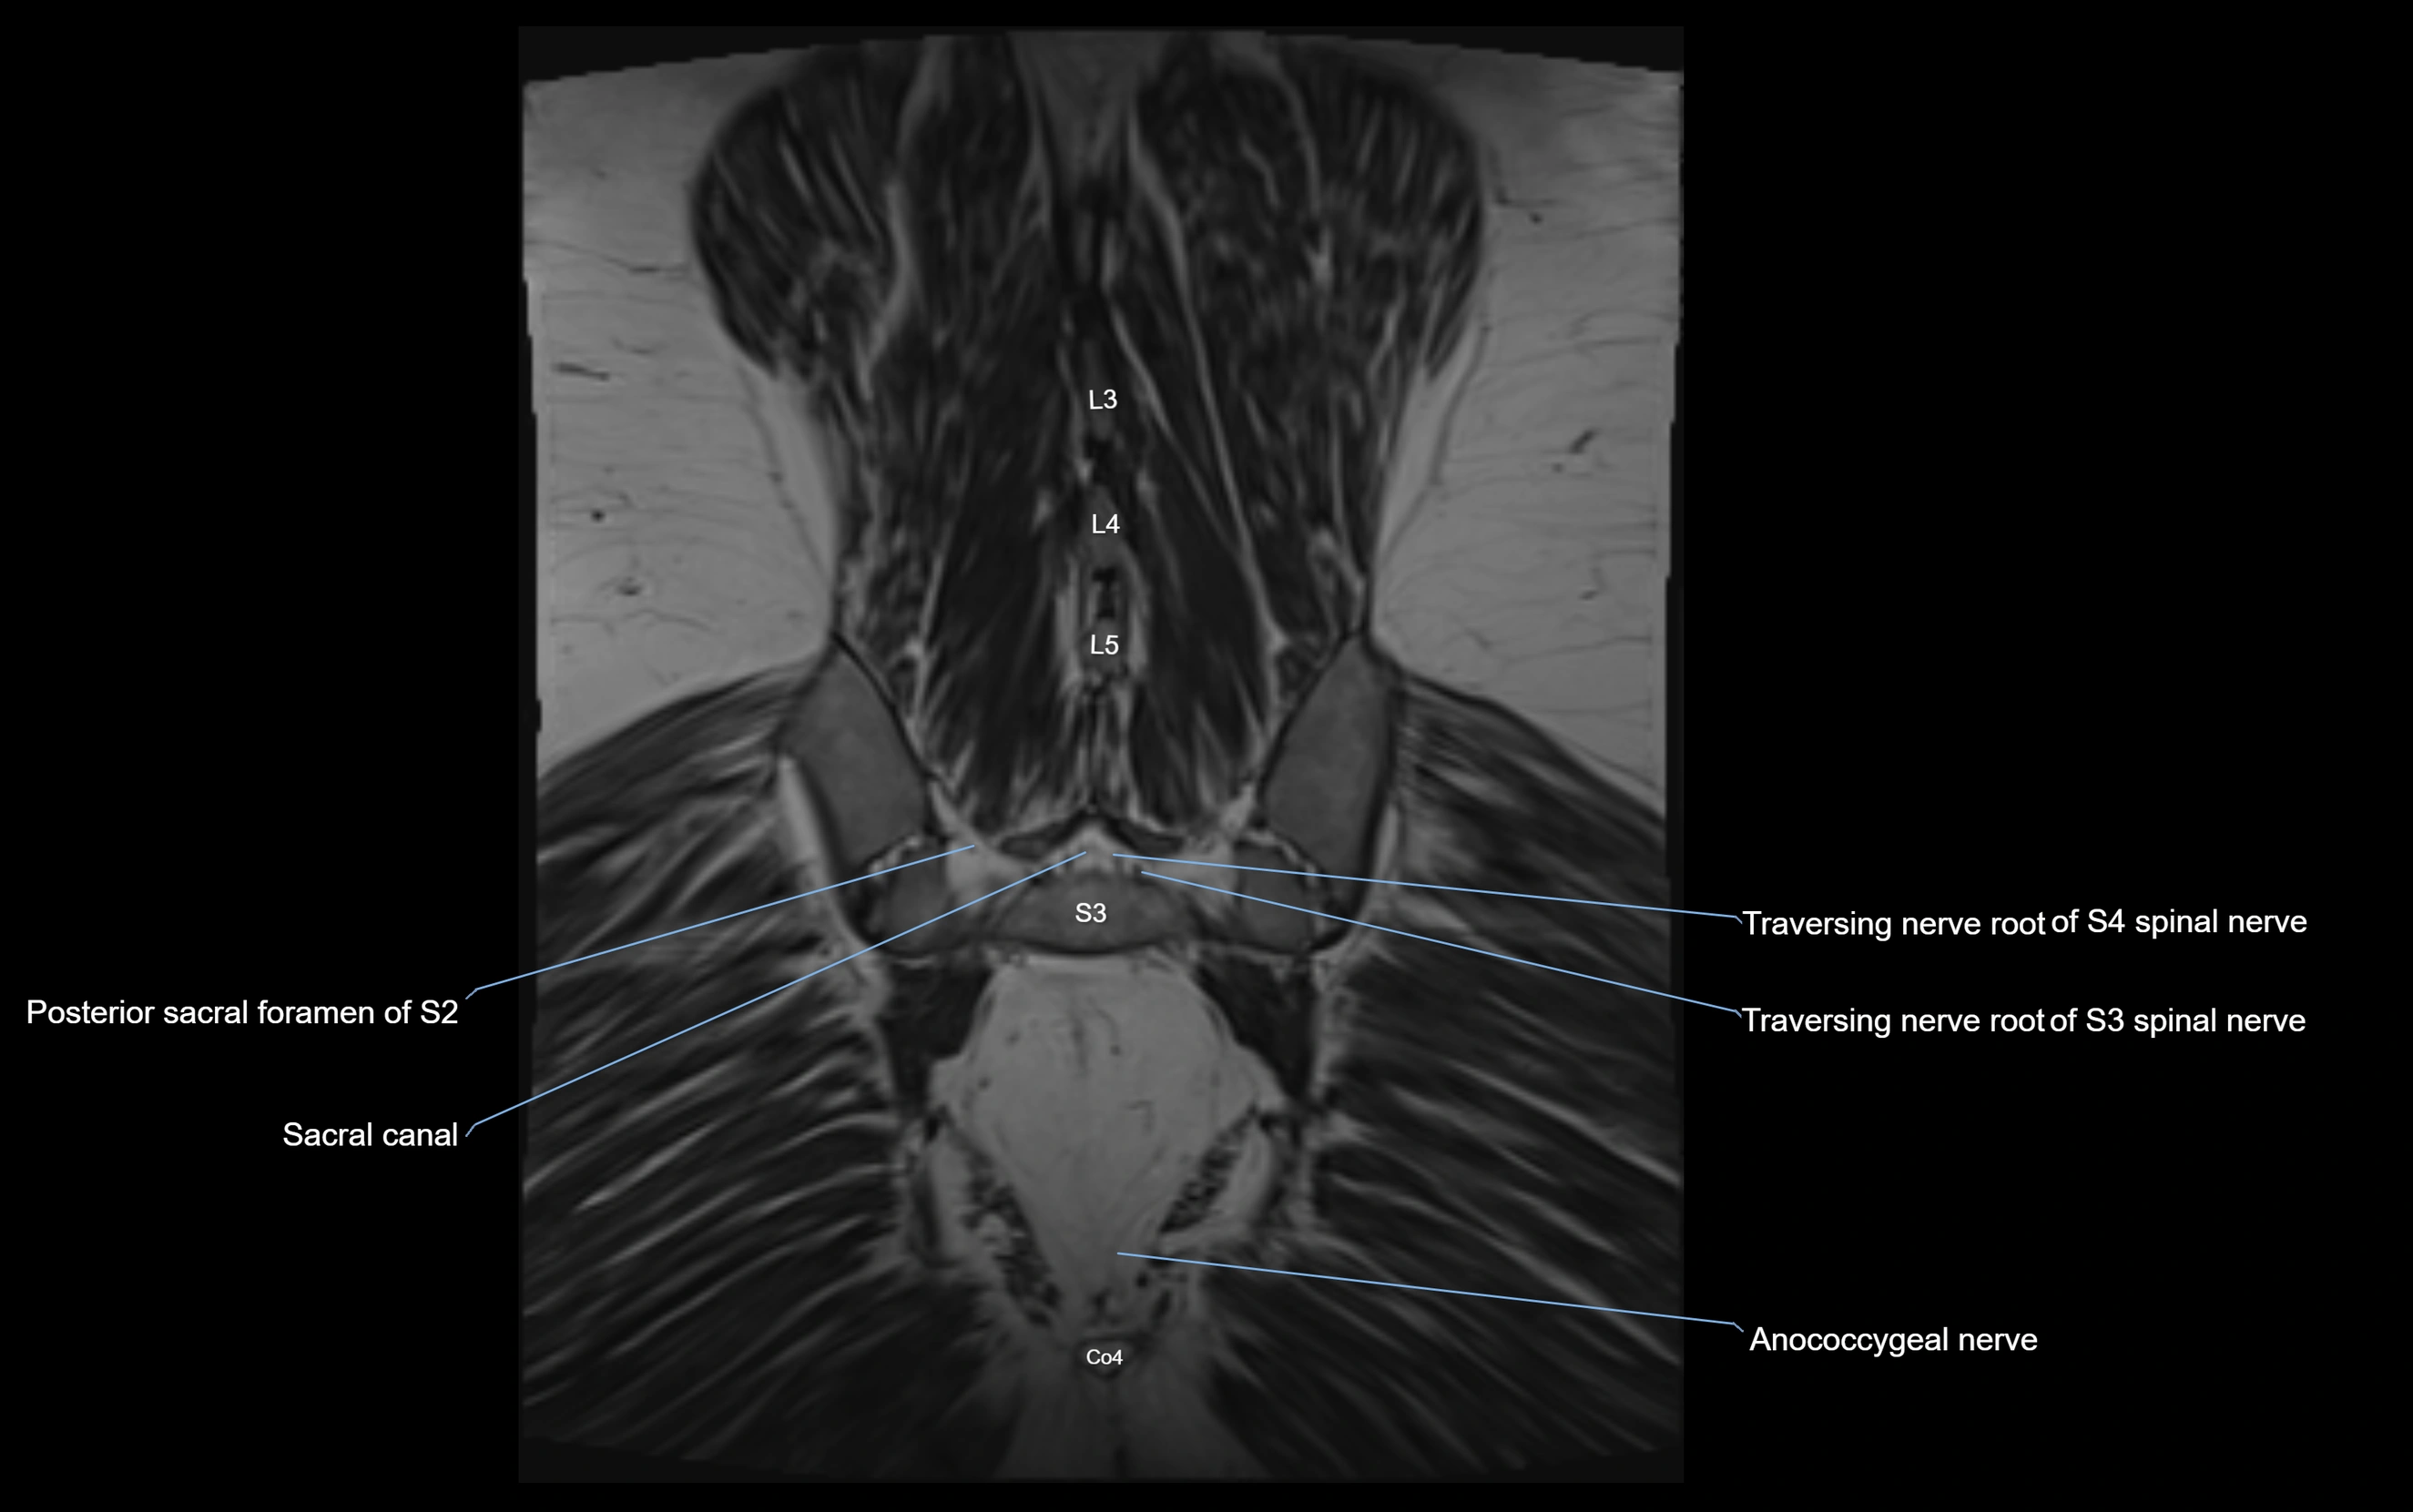

MRI image

image